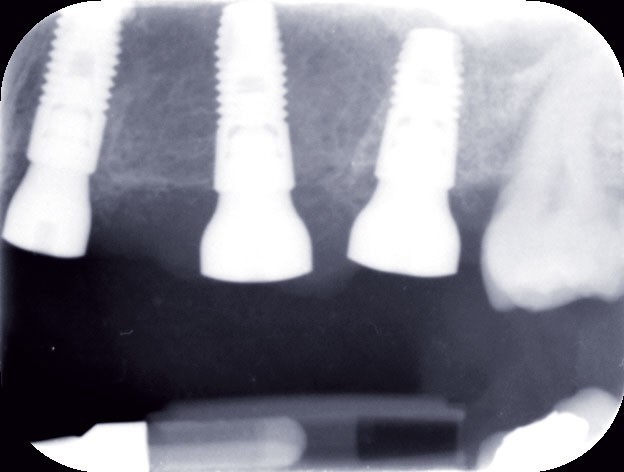

Le modèle de travail est fabriqué au laboratoire, des piliers CFAO Atlantis™ sont réalisés en fonction du bridge antagoniste transitoire.